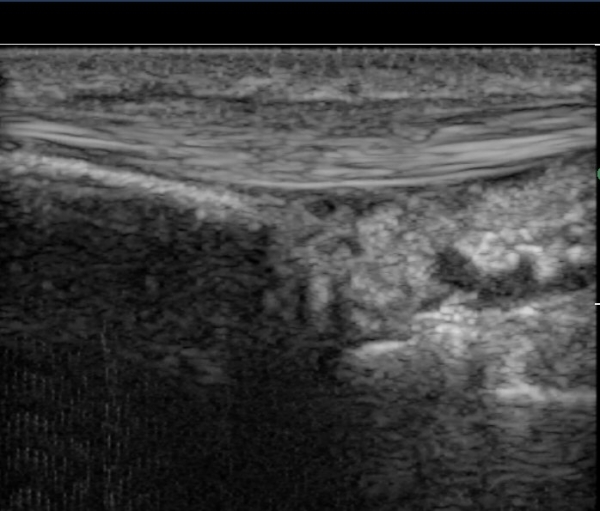

¿ä°ñ °æ»óµ¹±â ºÎÀ§¿¡¼­ tunnel I Ⱦ´Ü¸é°Ë»ç¿¡¼­ ´Ü¹«Áö½ÅÀü°Ç(EPB)ÀÇ ºÎÁ¾ ¹×

°ÇÁÖÀ§ ¼ö¾×Àú·ù°¡ °üÂûµÊ(»çÁø 1, 2)

ŽÃËÀÚ¸¦ ¾à°£ ¸»´ÜÀ¸·Î À̵¿ÇÏ´Ï ´Ü¹«Áö½ÅÀü°Ç(EPB)ÀÇ ºÎÁ¾ ¹×°ÇÁÖÀ§ ¼ö¾×Àú·ù°¡ °üÂûµÊ(»çÁø 3)

´Ü¹«Áö½ÅÀü°Ç(EPB) Á¾´Ü¸é°Ë»ç¿¡¼­ °ÇÀÇ ºÎÁ¾ ¹×°ÇÁÖÀ§ ¼ö¾×Àú·ù°¡ °üÂûµÊ(»çÁø 4)

ÃÊÀ½ÆÄ À¯µµÇÏ ÁÖ»çÄ¡·á »çÁø¿¡¼­ ÁÖ»ç ¹Ù´ÃÀÌ °ÇÁÖÀ§ ºÎÁ¾ ºÎÀ§¿¡ Á¤È®È÷ À§Ä¡ÇÔ(»çÁø 5, ÷ºÎÆÄÀÏ)